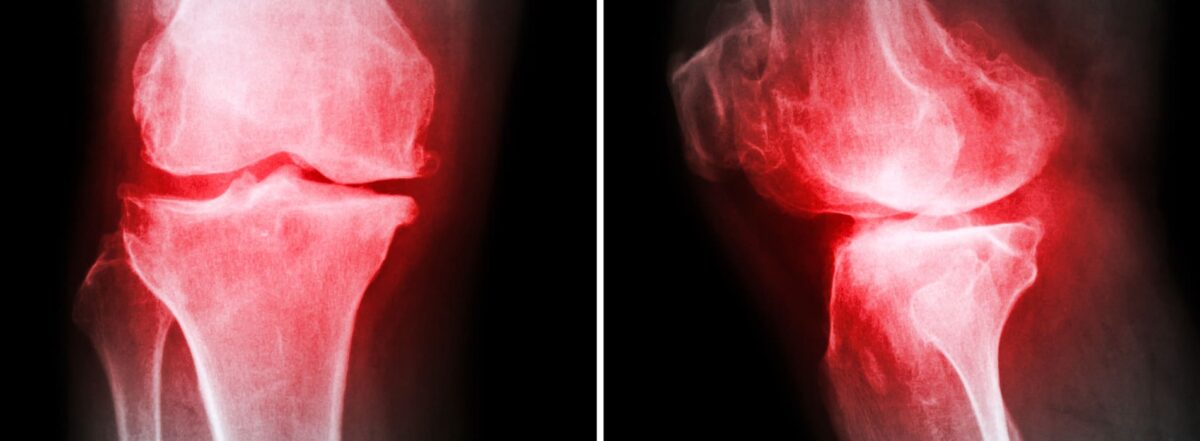

It is equally important to discuss the mechanics of arthritis. Studies have found that those who are only 10 kilograms overweight may place an additional strain of up to 30 kilograms upon the joints throughout their hips and legs.

This pressure will then result in excessive levels of wear and tear, eventually leading to a breakdown in the cartilage that cushions the joints and bones. If two bones begin to rub against one another, even mild symptoms of arthritis can be dramatically exacerbated.